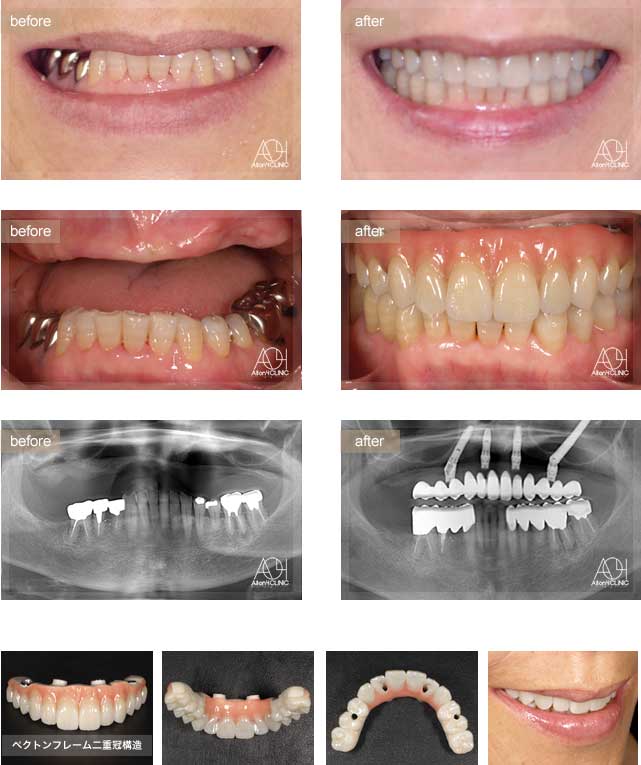

Treatment : All-on-4 zygoma

- Upper All-on-4

- Lower All-on-4

Age : 56 Sex : 男 S.T

| 主訴 | 仕事が忙しく歯には全く関心が無く、とうとう食事が困難になり治療を受ける事を決意。 |

| 治療内容 | ガイデッドサージェリーにてインプラント埋入。極めて骨量が少ないためザイゴマインプラントにて治療 |

| 治療費(総額) | ¥7,200,000(税抜)『モニター割引適用』 |

| リスク | 治療後の口腔管理が不適切な場合、埋入したインプラント周囲に感染・炎症を起こし、脱落する可能性がございます。 |